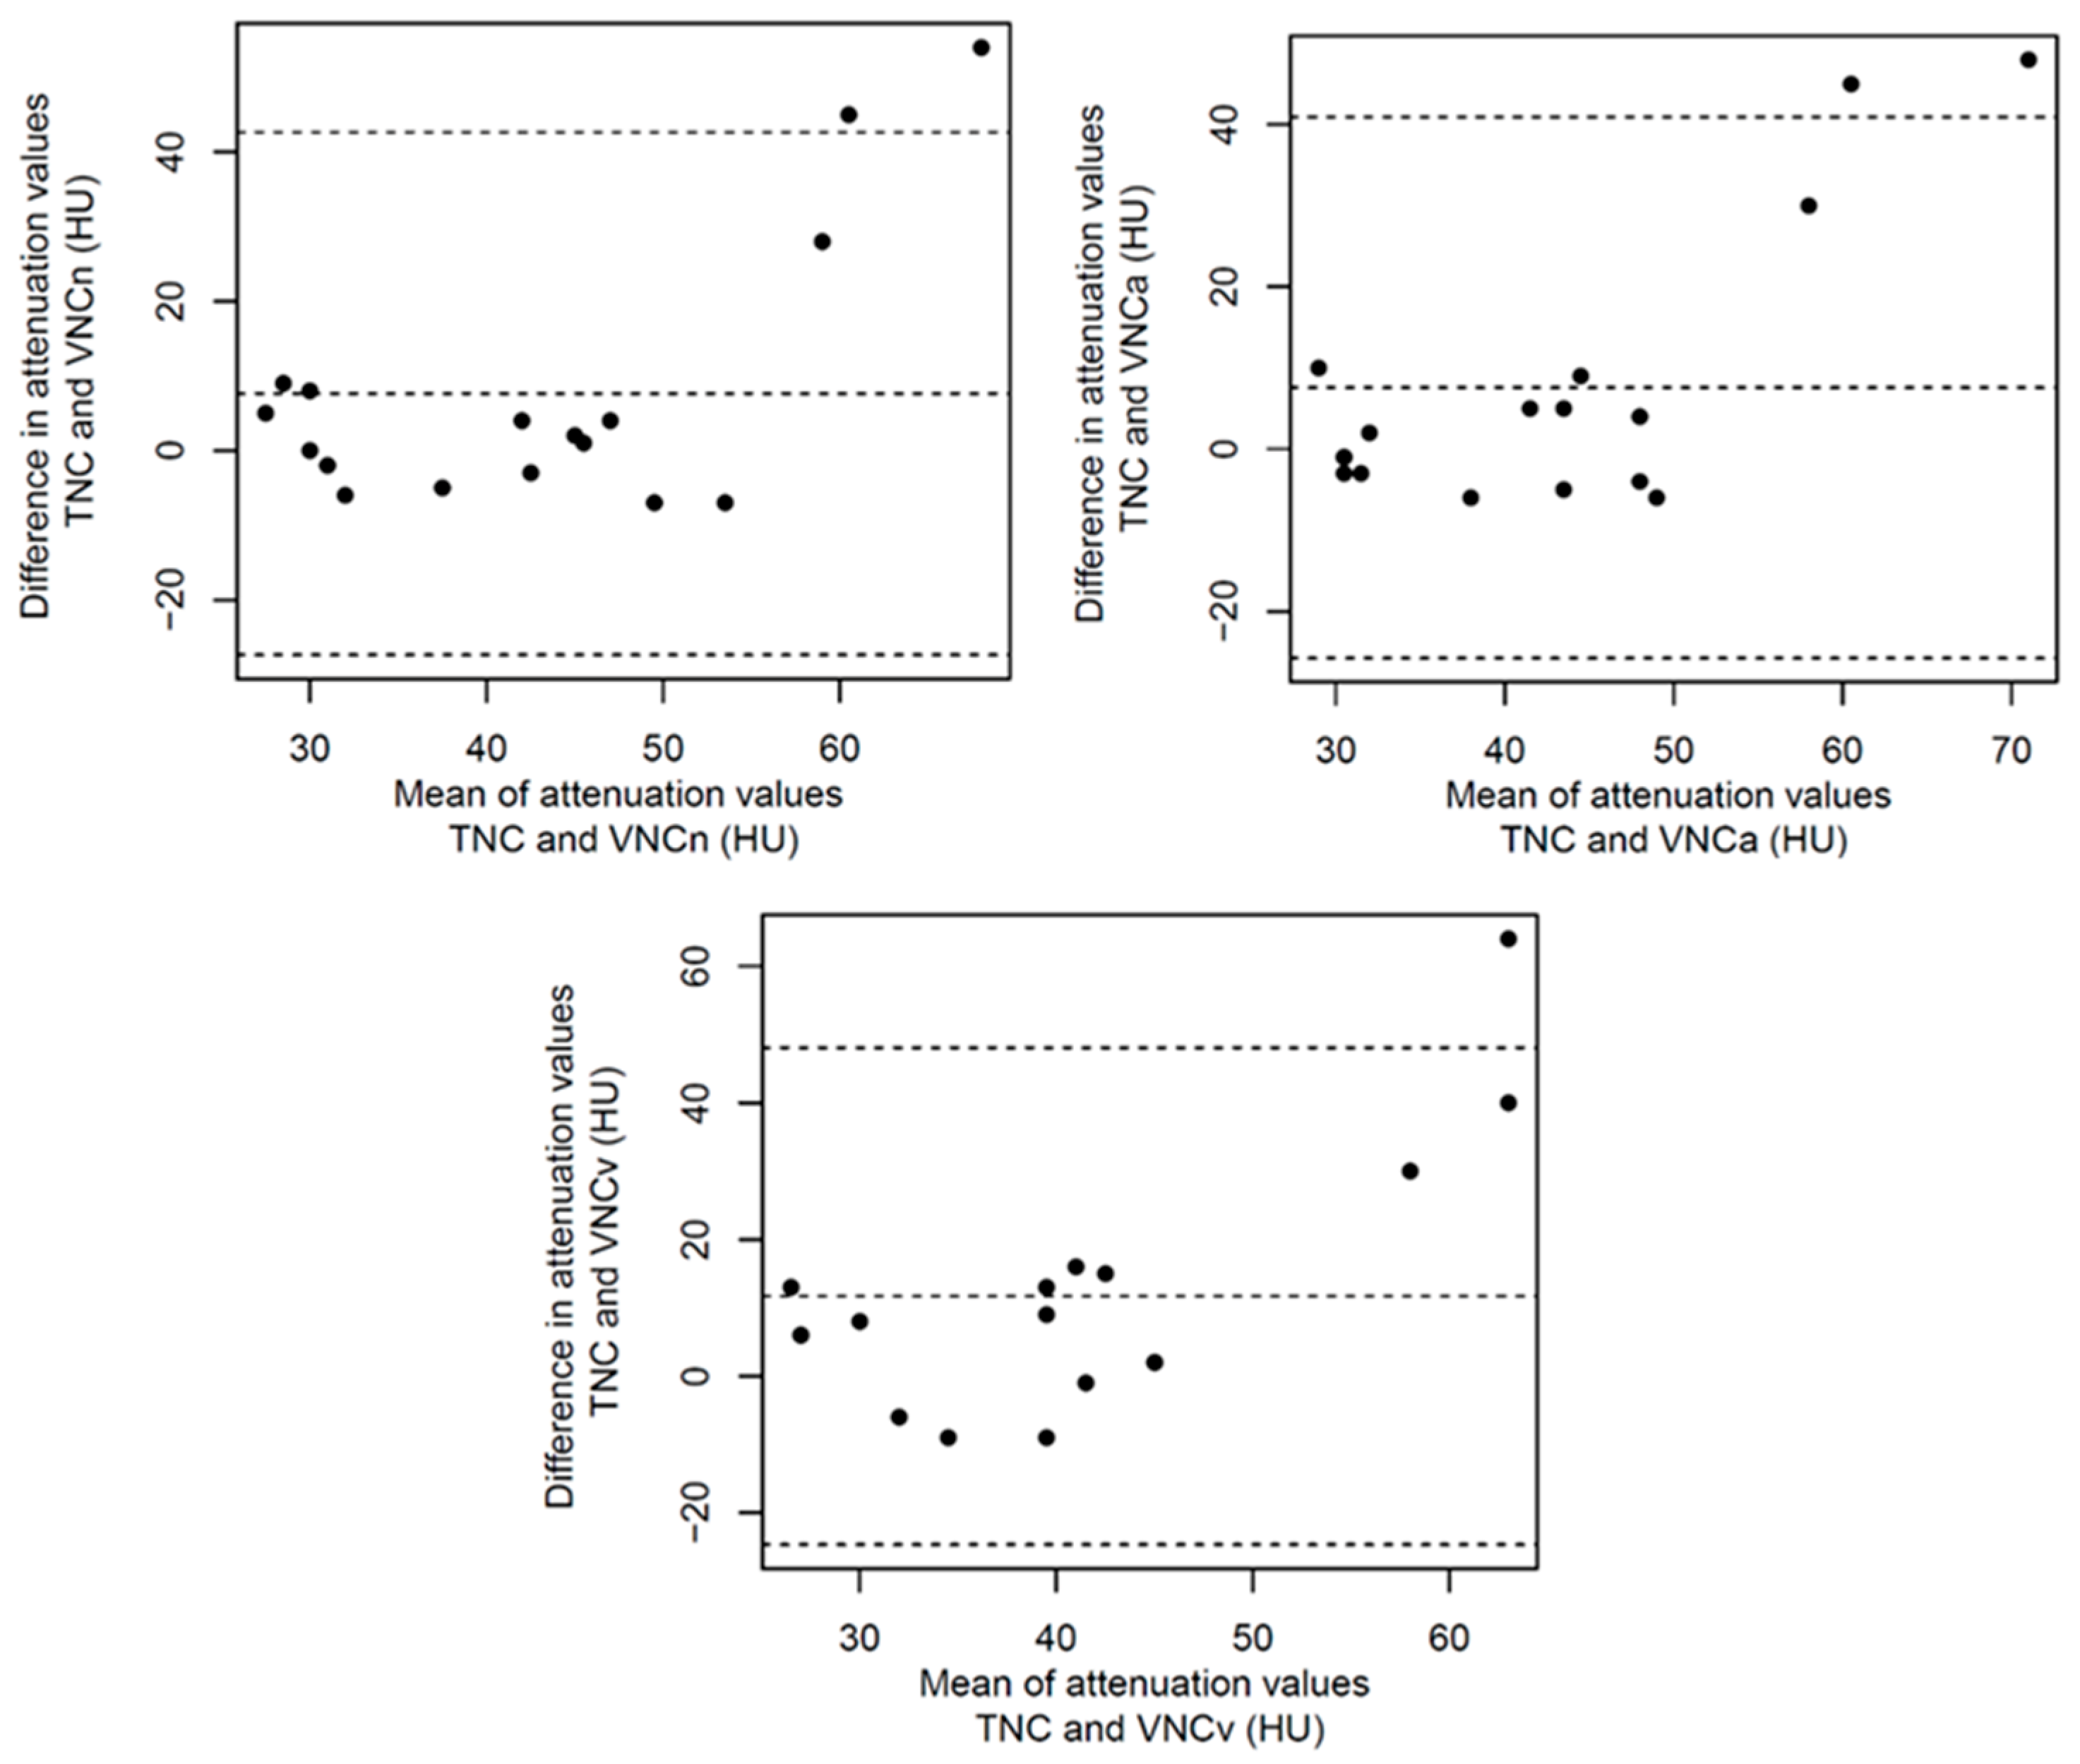

3. Results

3.2. Structured Measurement

4. Discussion